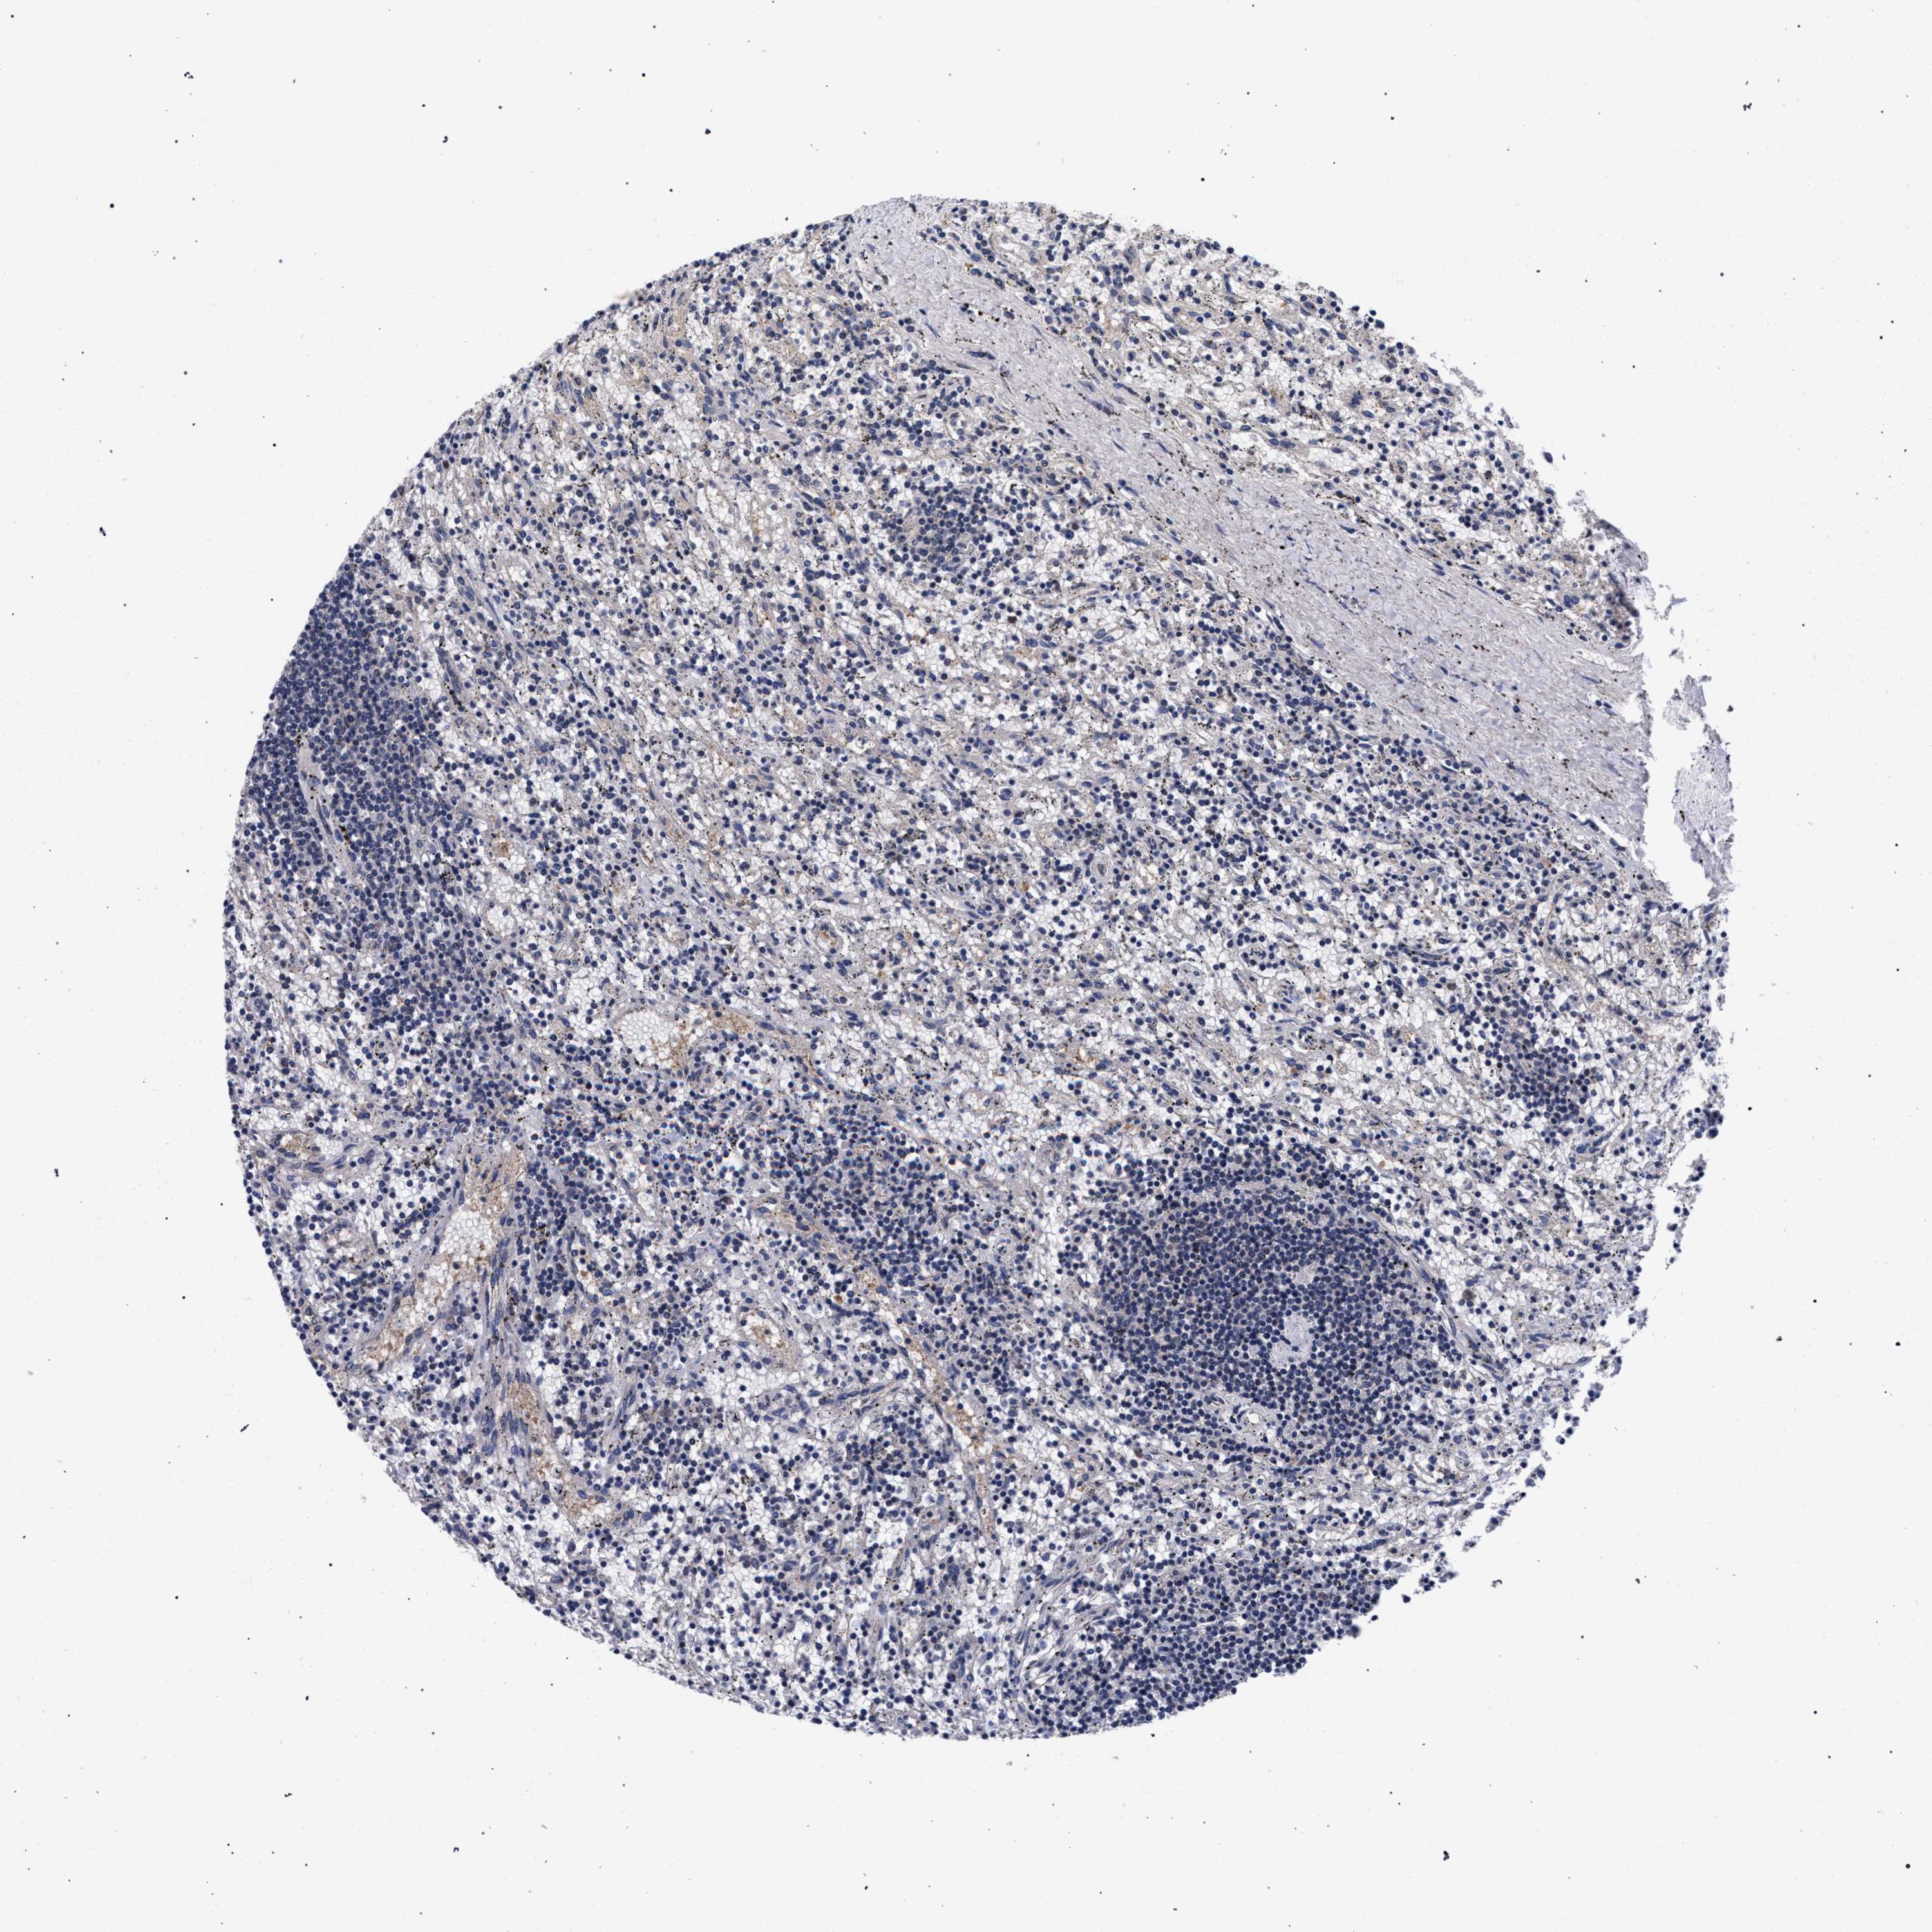

CANCER LYMPHOMA Show tissue menu

LYMPHOMA - Protein expressioni

A mouse-over function shows sample information and annotation data. Click on an image to view it in a full screen mode. Samples can be filtered based on level of antibody staining by selecting one or several of the following categories: high, medium, low and not detected. The assay and annotation is described here.

Each image is clickable and will lead to virtual microscopy that enables deeper exploration of all samples and also displays staining intensity scores, fraction scores and subcellular localization as well as patient and tissue information for each sample.

Hodgkin's disease, NOS

Malignant lymphoma, non-Hodgkin's type, High grade

Malignant lymphoma, non-Hodgkin's type, Low grade